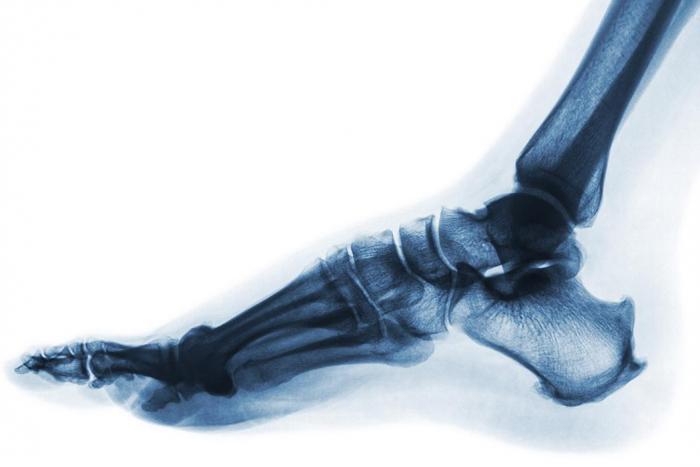

Diplomado en Urgencias Traumatológicas de Pie y Tobillo

Uno de los motivos más frecuentes en las consultas de urgencias de los hospitales son las fracturas y otras patologías agudas traumatológicas.

Aprender a identificar y atender las lesiones más frecuentes en la articulación del tobillo y del pie